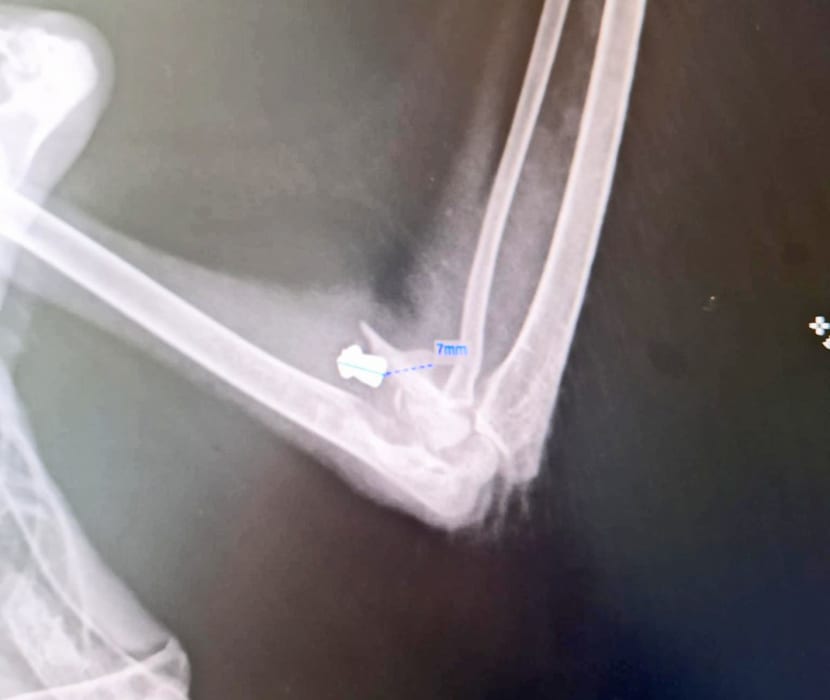

TKO PUCA NA GALEBOVE? Na pulskom Vidikovcu zrnom od sedam milimetara ustrijeljena mlada ptica

Na pulskom Vidikovcu, pokraj dječjeg igrališta 18. travnja pronađen je mladi galeb s vidljivom ozljedom na krilu.

Puležanka koja ga je pronašla, odnijela ga je kod veterinara, te je utvrđeno kako galeb ima metak u krilu i to od sedam milimetara.

Kako doznajemo od osoba koje su preuzele brigu o ptici, on je prebačen u Zagreb, gdje će operaciju uklanjanja metka iz krila obaviti doktorica Ingeborg Bata.